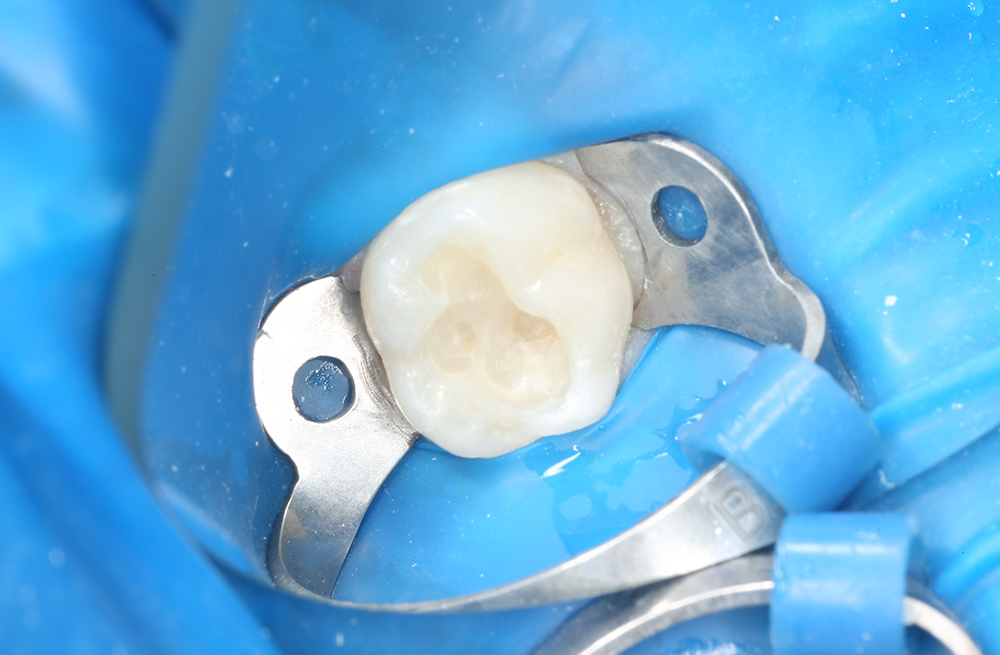

Восстановление жевательной поверхности постоянного зуба после кариозного разрушения у подростка